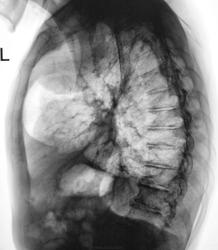

Томограммы от "вчера"

Томограммы в боковой проекции.

Наличие плевральных изменений , развившихся за последние 1,5 года в различных отделах левого гемитораска, позволяет мне считать, что округлая тень в левом легком есть осумкованный верхушечный плеврит, который сформировался у больного в период вспышки туберкулезного процесса в S 1-2 слева. Напоминает и бронхогенную кисту Жду мнения коллег. С уважением Nik

по КСС прошу объяснить видимые тени в позвонках. (см. рисунок). С уважением Nikolas

Изменения в позвонках были замечены. Но, мы решили не затягивать процесс дообследования, так как госпитализация в областную туб больницу была оперативно решена. А там, диагностические возможности намного выше чем наши.

Интересно, чем сердце успокоилось, но мне кажется больше за обострение туб процесса, тк на фоне кальцинатов свежая инфильтрация (на томограммах), но и новообразование "мерещится". Биопсию не проводили в ОПТД? Ведь на фоне старых очагов часто через 20 лет рачок вырастает.